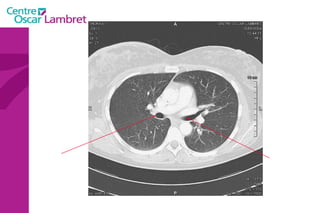

Le médiastin C'est l’espace au centre du thorax. Il est situé en avant de la colonne vertébrale et peut être divisé en plusieurs quadrants.  Il est divisé, par convention, en : médiastin postérieur :  contenant notamment  l’oesophage et l’aorte descendante.  médiastin moyen :  contenant les voies aériennes supérieures : trachée et sa division (carène).  médiastin antérieur :  contenant le cœur, l’aorte ascendante, les artères pulmonaires et la veine cave supérieure.

Le médiastin Le médiastin   antérieur  comprend : L’aorte ascendante Le tronc pulmonaire La veine cave supérieure Les cavités cardiaques sauf l’atrium gauche La loge thymique

Le médiastin Le  médiastin moyen  comprend : La trachée La carène Les pédicules pulmonaires : Les bronches souches Les veines et les artères pulmonaires Le segment horizontal de la crosse de l’aorte Le Tronc Artériel Brachio-Céphalique L’artère carotide primitive gauche La crosse de la grande veine azygos

Le médiastin Le médiastin  postérieur  comprend : Le canal thoracique La grande veine azygos et les veines hémi azygos L’œsophage L’aorte descendante et ses branches

La ligne médiastinale antérieure (jonction des deux languettes pulmonaires antérieures avec 4 feuillets pleuraux en arrière du sternum et en avant du médiastin).  •  La ligne médiastinale postérieure (jonction des deux languettes pulmonaires postérieures et supérieures en arrière du médiastin). Le médiastin

Ligne médiastinale postérieure Ligne médiastinale antérieure Le médiastin